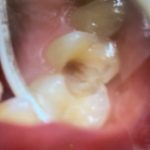

虫歯の治療の写真です。結構やられてますね😅

でもきれいに保険治療で治ります👍